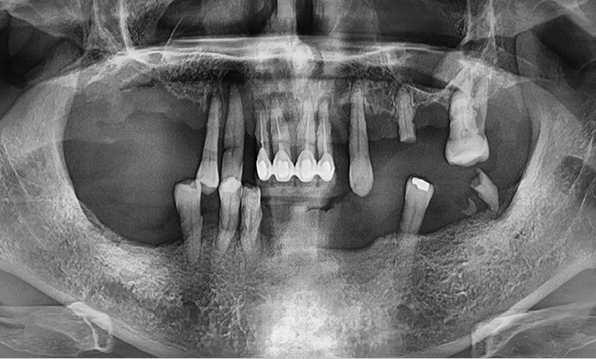

전체 임플란트는 위턱과 아래턱의 교합, 잇몸뼈의 상태 및

얼굴 변화 등 모든 것을 고려해 식립해야 합니다.

서울더자연치과는 3D 디지털 기술의 정밀 진단을 바탕으로

수술 계획을 세워 수술을 집도합니다.

잇몸뼈가 얇은 상태

잇몸뼈 충분히 이식 후 임플란트 식립

성공을 위한 노하우, 잇몸뼈 재건 기술

전체 임플란트를 해야하는 환자들은

대부분 고령의 환자들로 오랜 틀니 사용

또는 노화로 인해 치조골이

거의 남아있지 않는 경우가 많습니다.

이 때, 치조골 이식을 병행하여 잇몸뼈 재건 후 안정적인 임플란트 식립을 하고 있습니다.

치료기간 : 2021.04.12~2021.09.15